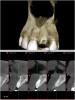

fmn Опубликовано 6 октября, 2013 Поделиться Опубликовано 6 октября, 2013 Здравствуйте, уважаемые коллеги. это мой первый пост на этом ресурсе. так что прошу не пинать сильно не судить строго. Вчера делал небольшую хирургию, надеюсь, интересную для посетителей форума. Пациентка - чудесная женщина средних лет пожаловалась на перелом корня центрального резца, который до этого был восстановлен композитной реставрацией на внутриканальном штифте. На КТ - небольшая фенестрация вестибулярной стенки и потеря костной ткани в области дистальной контактной поверхности, что склонило чашу весов в процессе принятия решения в сторону отсроченной имплантации. По поводу выбора техники я долго колебался - первоначально предложил удаление и аугментацию ССТ тоннельным методом с вестибулярной стороны. затем передумал и, в итоге решил отложить это до этапа имплантации (т.к. дистальный сосочек может уйти и на этапе имплантации будет возможность его аугментировать), а в качестве подготовки провести аугментацию костным материалом и толстым СДТ. Ссылка на комментарий

carloss Опубликовано 7 октября, 2013 Поделиться Опубликовано 7 октября, 2013 (изменено) Итерпроксимальный дефект, это дистально 21?.. А вестибулярно, вроде лефекта я не вижуТак там минус 1мм, из того, что видно по снимку, можно было сст вкруговую подлодить.. В любом случае, теперь там кость не нарастёт Изменено 7 октября, 2013 пользователем carloss Ссылка на комментарий

fmn Опубликовано 7 октября, 2013 Автор Поделиться Опубликовано 7 октября, 2013 Итерпроксимальный дефект, это дистально 21?.. А вестибулярно, вроде лефекта я не вижуТак там минус 1мм, из того, что видно по снимку, можно было сст вкруговую подлодить.. В любом случае, теперь там кость не нарастётДа, я имел ввиду дефект дистально 21. А минус 1мм был бы и при установке винта, плюс ССТ я и так планировал класть во время имплантации. Ссылка на комментарий